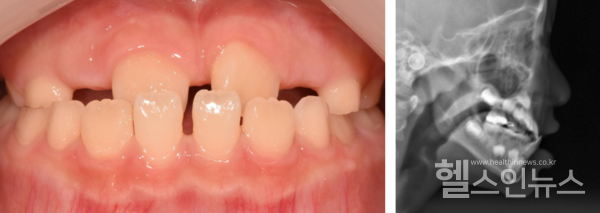

즉각적인 치료가 필요할 때도 있다. 대표적으로, 윗턱보다 아래턱이 앞으로 나와 윗니와 아랫니가 거꾸로 물리게 되는 ‘반대교합’의 경우다. 반대교합은 만 7~8세 경 영구치가 맹출하는 시기에 주로 치료하지만, 정도가 심한 경우 유치열기(생후 6개월로부터 최초 영구치가 나타나기 직전까지의 기간)에서도 치료한다.

이 교수는 “유치열기에는 아래턱보다 윗턱의 성장이 중요하다”라며, “반대교합이 있으면 아래턱이 윗턱의 성장을 방해하므로 윗턱 성장을 촉진하는 치료를 주로 진행한다”라고 말했다.

반대교합과는 반대로 아래턱이 윗턱에 비해 성장하지 못해 소위 ‘무턱’이라 불리는 ‘하악후퇴증’도 있다. 이 경우, 윗니가 아랫니를 깊게 덮는 ‘과개교합’이나 턱관절 장애를 동반하기도 한다. 하악후퇴증의 치료는 윗턱 성장을 억제하고 아래턱 성장을 촉진하는 악정형치료를 진행한다.